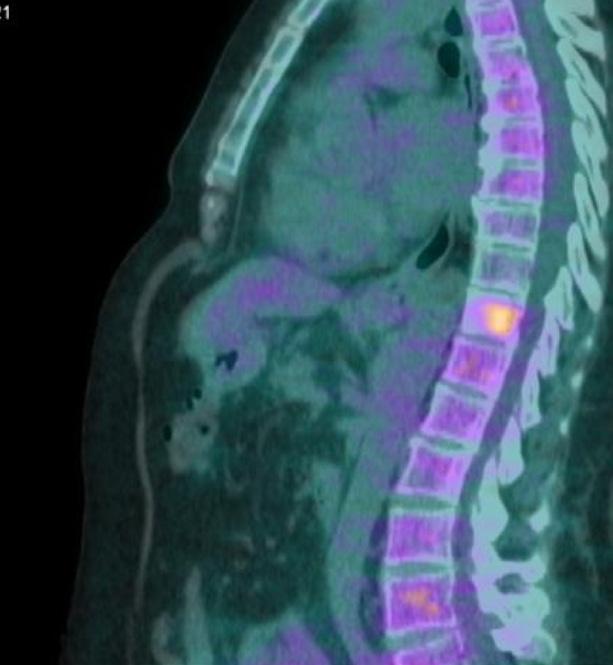

3 cicli di trattamento, alla PET di Febbraio 2019 (figura 2) si è dimostrata una sensibile regressione della lesione mammaria che presenta un SUV massimo pari a 2,9 vs 5,6 del precedente controllo; in sede ascellare di sinistra, apprezzabile sovracentimetrico linfonodo, modestamente captante il tracciante metabolico (SUV massimo pari a 1,7). Per quanto concerne le lesioni scheletriche descritte nel corso del precedente test, permane caratterizzato da modesta attività metabolica, esclusivamente un’unica lesione posta nel soma di D2. Non si risconoscono aree di accumulo di nuova comparsa.

2. PET dopo 3 cicli di ct con TXT trastuzumab e pertuzumab.